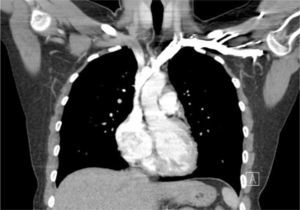

TOMOGRAFÍA COMPUTARIZADA AXIAL DEL TÓRAX

Se muestra cómo los vasos sanguíneos mamarios, pleura medial a la derecha, vena cava superior, aorta ascendente, y vena ácigos son todas similares en el primer y segundo plano. Los catéteres en cada una de estas diferentes estructuras no se distinguen claramente en el plano de la imagen (Radiografía de tórax).

Ante esta situación, los catéteres son fácilmente reconocidos como mal colocados y generalmente no se necesita el consejo de un especialista antes de su revisión, uso o retiro. Los catéteres pueden estar en una posición obviamente incorrecta fuera de la vena o puede parecer que siguen una ruta normal aproximada a través de la radiografía torácica, pero no están correctamente colocados en la vena cava superior. Las imágenes de tomografía computarizada axial muestran que no se pueden distinguir un catéter en una imagen plana el espacio pleural derecho, los vasos mamarios internos derechos, el sistema ácigo, la aorta ascendente o el mediastino (Figura 8). La radiografía torácica sólo puede confirmar el paso del catéter central, plegamientos de éste o complicaciones de procedimiento.